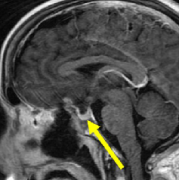

鞍结节是垂体窝前微微隆起的骨质,高度和宽度只有几个毫米。从这个区域起源的肿瘤在引起临床症状时通常直径已达2~4cm。由于鞍区体积相对较小,这些肿瘤在硬膜上的附着处向前可伸至...